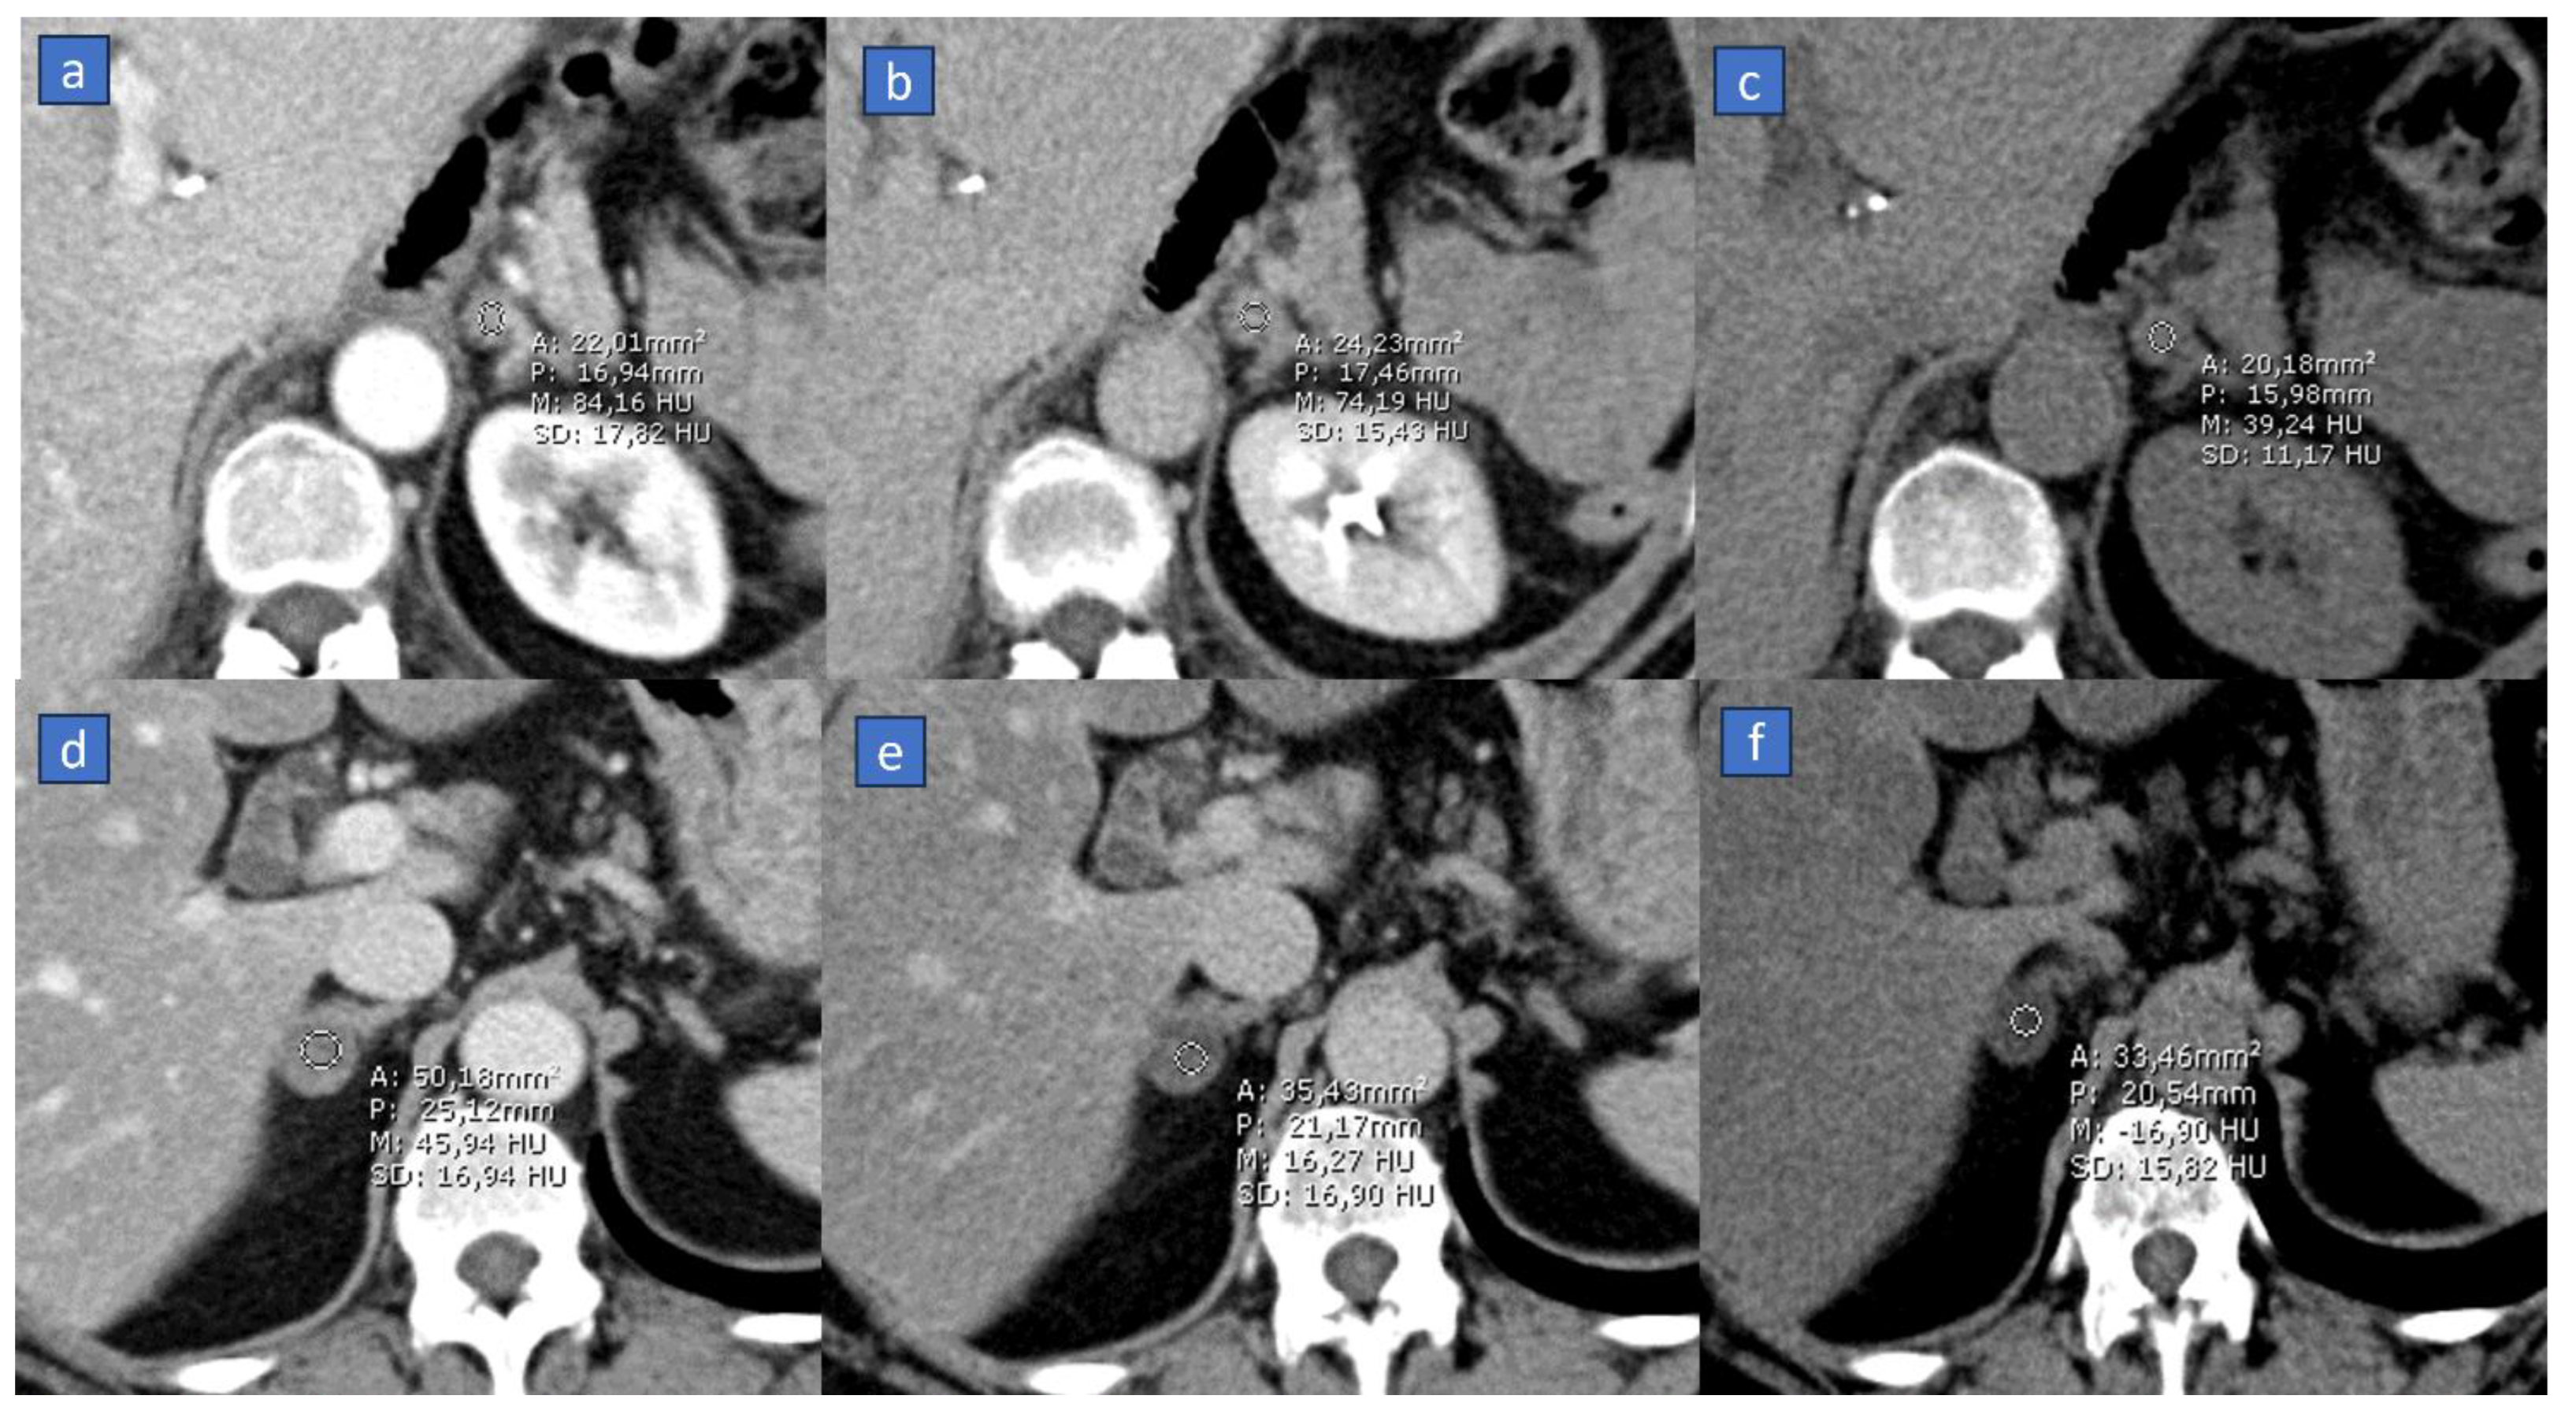

4. Virtual Monoenergetic

4.1. Better Conspicuity of Lesions

4.2. Less Contrast Material